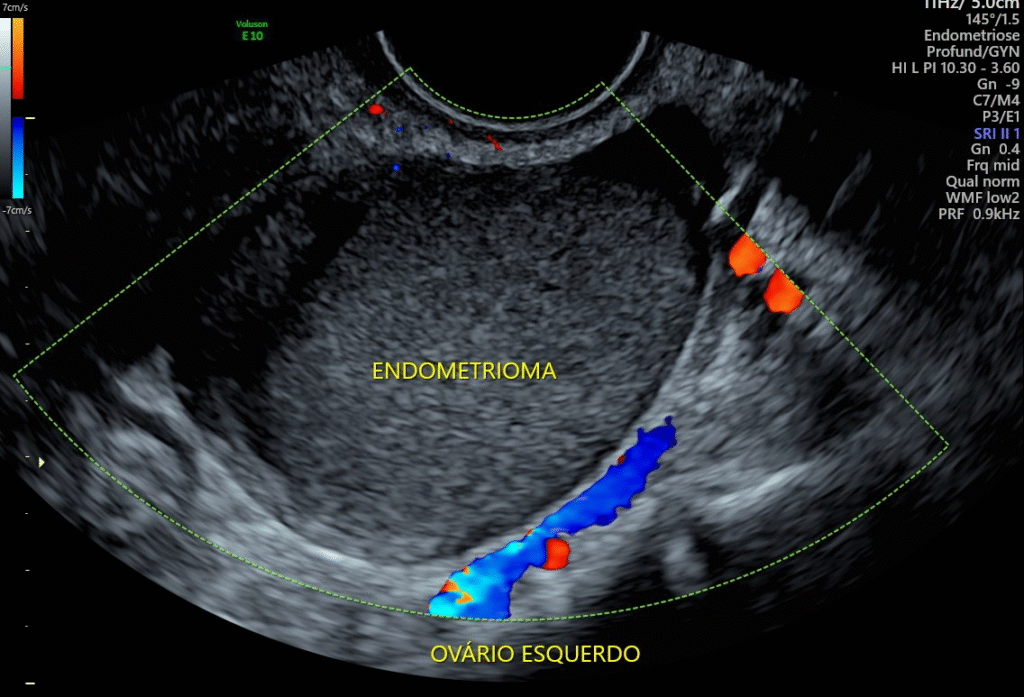

A prática sexual regular, por si só, não é responsável pelo surgimento da endometriose. Essa condição ocorre quando o tecido semelhante ao endométrio — que deveria crescer apenas dentro do útero — começa a se desenvolver fora dele, em locais como ovários, trompas e intestinos. Essa proliferação indevida pode provocar dor pélvica intensa, cólicas severas, sangramentos irregulares e desconforto durante a relação sexual.

A endometriose não tem cura definitiva, mas há tratamentos eficazes para aliviar os sintomas e melhorar a qualidade de vida das pacientes. Quanto mais cedo for diagnosticada, maiores as chances de controle e de evitar complicações mais graves, como a infertilidade. Por isso, ao perceber dores intensas durante o ciclo menstrual ou na relação sexual, é fundamental procurar um ginecologista.